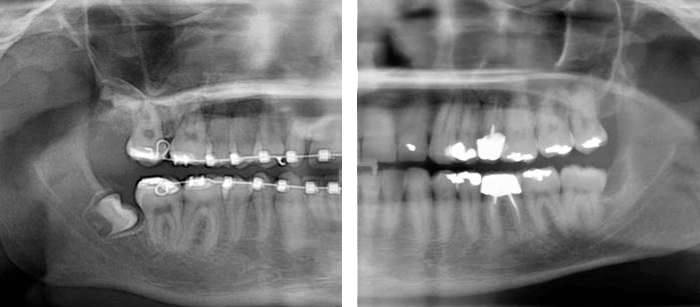

Per mezzo delle radiografie panoramiche e laterali e grazie a sofisticati programmi di calcolo della crescita, siamo in grado di predeterminare se lo spazio osseo sarà sufficiente per accogliere il dente del giudizio senza problemi.

ESEMPIO DI DIFFERENZA TRA GERME DI DENTE DEL GIUDIZIO A 12 ANNI (SINISTRA) E DENTE DEL GIUDIZIO FORMATO A 40 ANNI CON PROBLEMI DI LESIONE OSSEA (DESTRA)